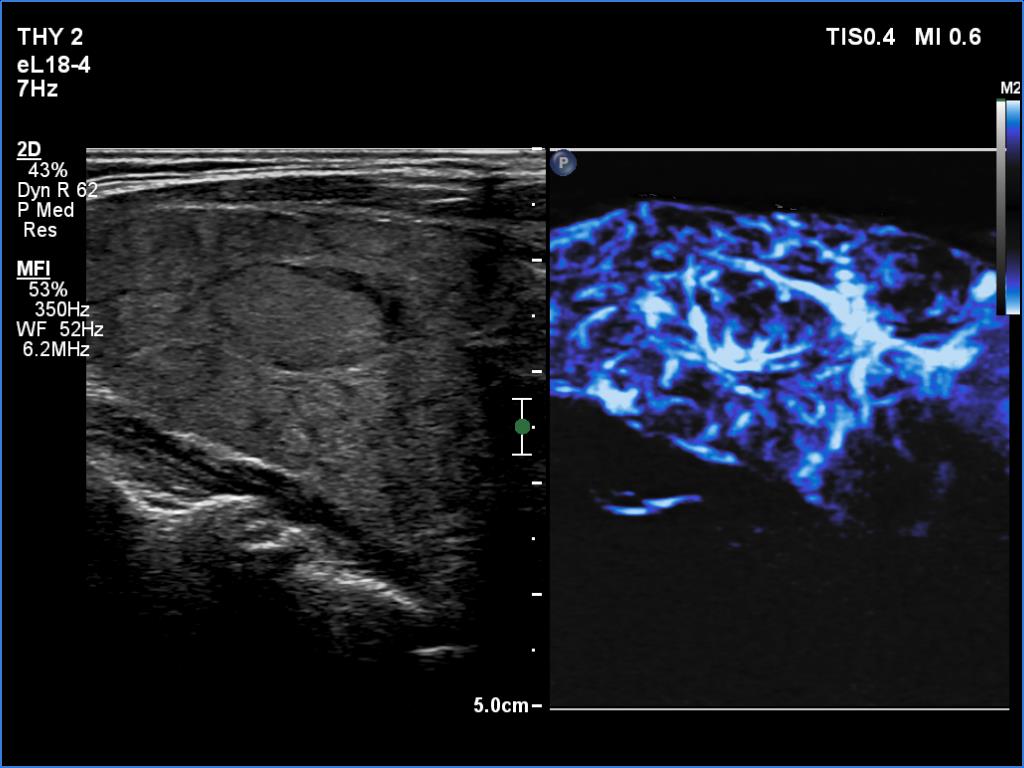

Lymphocytic thyroiditis - case 609

Follow-up investigation 6 years after the first visit (ultrasonographic picture 13)

Left lobe, longitudinal scan, microflow imaging. The micronodular form is even better seen with this technique.